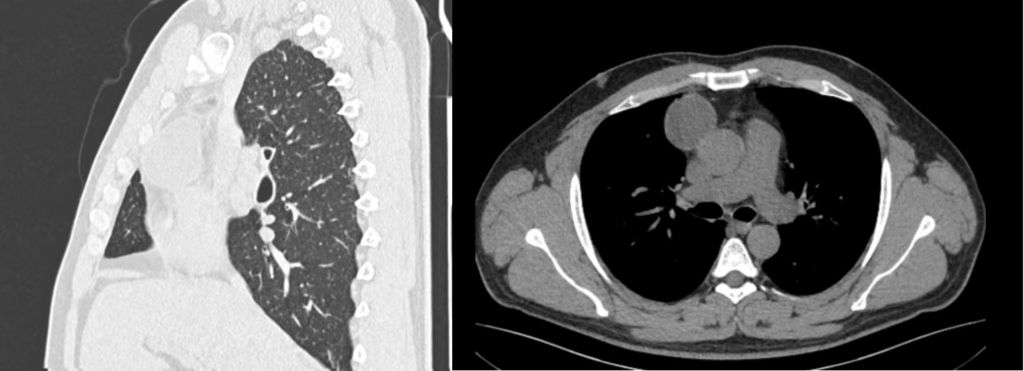

患者为33岁年轻男性患者,于体检时发现前上纵隔肿瘤,直径约5-6cm,为将患者的创伤降到最低,同时兼顾术后快速康复及美观,最大限度的节约诊疗费用,经过详细术前讨论及多学科会诊,韩锋主任及团队成员王青松、孙明德主治医师为患者实施三孔胸腔镜下纵隔肿瘤切除术。这项手术是通过3个直径仅1.2、1、0.5cm的胸壁操作孔完成的,较传统手术比较而言,传统手术切口(约20cm长)及常规胸腔镜小手术切口(1个约3-5cm长),创伤微小,使术后疼痛大大减轻,恢复也更快。胸外科团队经过充分的术前准备, 选择合理的切口设计,团队成员镜下配合流畅,历时仅半小时即顺利完成纵隔肿瘤切除术。术后6小时患者即可下床活动、进食,术后3天顺利出院。

术前影像